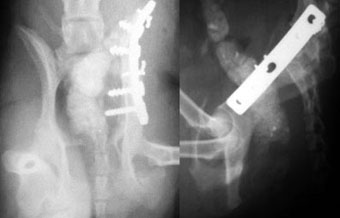

他院からの紹介症例

体重7kg、10か月齢の犬。

腸骨と坐骨の骨折と仙腸関節離断をおこしていました。

腸骨と坐骨はプレート法で整復固定し、仙腸関節離断は創外固定法で整復しました。

写真上段: 手術前

写真下段: 手術後